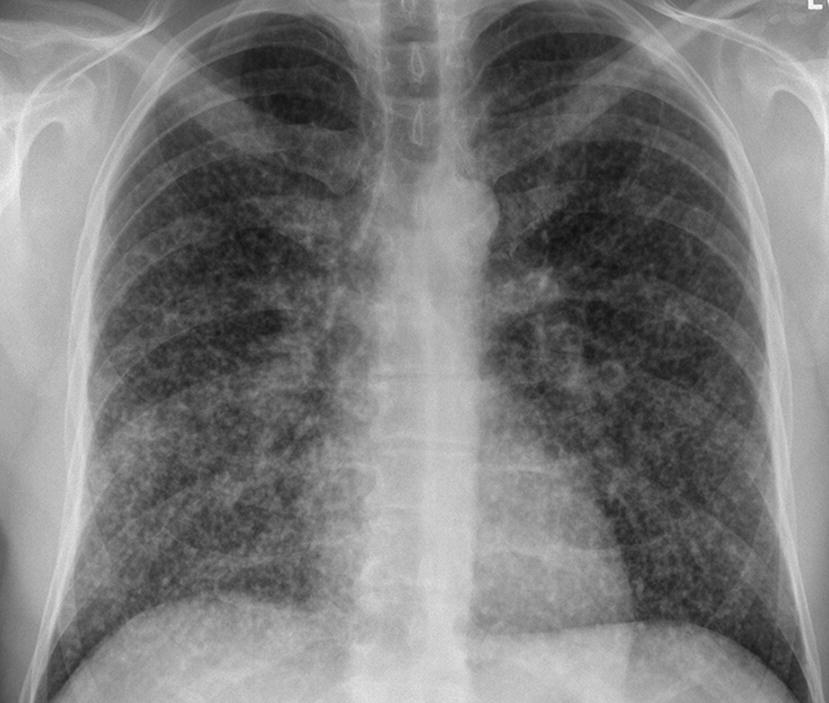

This may be used to describe a regional pattern or a diffuse pattern throughout the lungs. While this is a relatively common appearance on a chest radiograph very few diseases are confirmed to show this pattern pathologically. A reticulonodular interstitial pattern is an imaging descriptive term that can be used in thoracic radiographs or CT scans when are there is an overlap of reticular shadows with nodular shadows.

Reticulogranular ground-glass abnormalities increased attenuation of the lung tissue without distortion of the underlying blood vessels or bronchi are absent or minimal in IPF. It should be considered in patients with interstitial lung disease with bony involvement. The lung architecture is distorted in patients with moderate or severe disease burden with reduced lung volume and traction bronchiectasis especially at the lung bases.

Click to see full answer. This may be used to describe a regional pattern or a diffuse pattern throughout the lungs.

Dr Yair Glick and Dr Yuranga Weerakkody et al. Diagnosis is frequently delayed and prognosis is usually poor. Decreased lung volume and diffuse reticulonodular opacities. This may be used to describe a regional pattern or a diffuse pattern throughout the lungs. A reticulonodular interstitial pattern is produced by either overlap of reticular shadows or by the presence of reticular shadowing and pulmonary nodules. Interstitial lung disease includes more than 200 different conditions that cause inflammation and scarring around the balloon-like air sacs in your lungs called the alveoli. The scarring is called pulmonary fibrosisbreathing in dust or other particles in the air are responsible for some types of interstitial lung diseases.